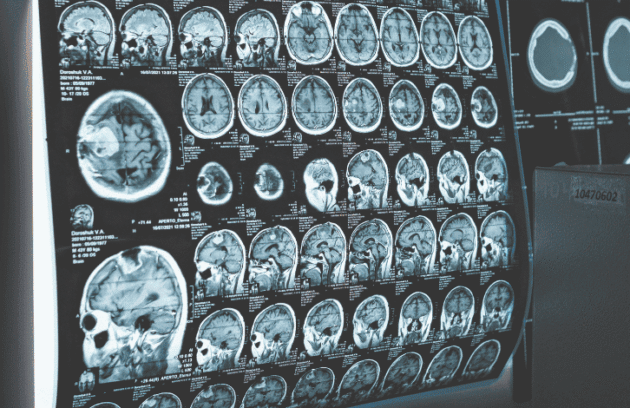

Um exame mostra que sim, existe a possibilidade de detectar alzheimer antes dos sintomas e agir de forma preventiva. Saiba…